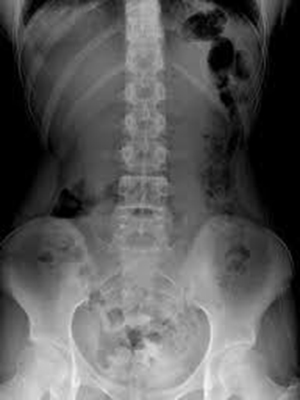

最新の技術を搭載したKONICA MINOLTA FPD(Flat Panel Detector)AeroDR使用

高精度・被ばく低減・時間短縮により患者様により優しい検査を実施しています。

放射線被ばくを約50%(当院比)することが可能となりました。

数秒で画像の確認ができるようになり検査時間や待ち時間を大幅に短縮することができるようになりました。

高画質、高精細なため微細な骨折や肺病変なども写し出すことが可能になり診断能も大きく向上します。